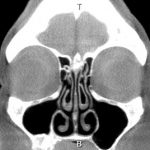

Os cornetos encolherão se o ar estiver quente e secretarão menos muco se o ar estiver úmido. A imagem abaixo mostra um nariz com cornetos saudáveis. Eles aparecem como estruturas cinzentas e encaracoladas em ambos os lados da linha média do septo nasal.